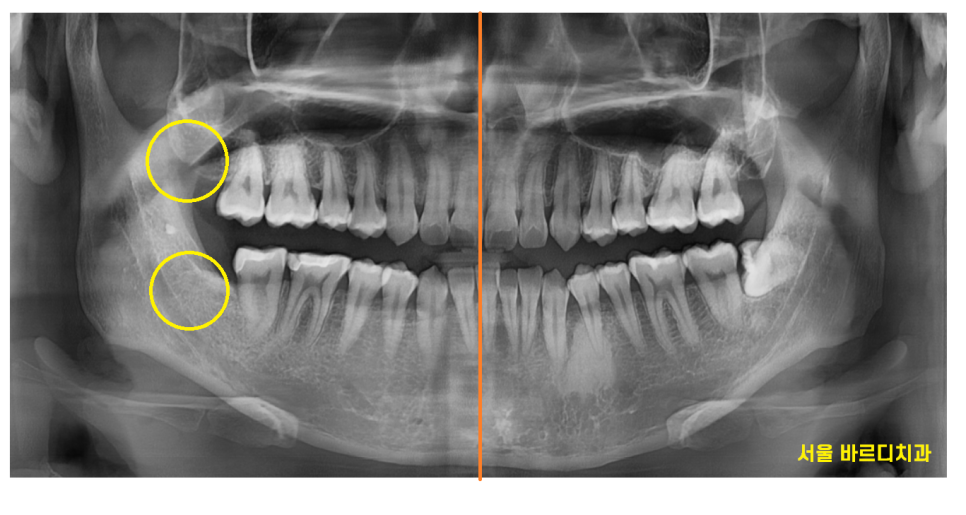

사진 속 4개의 사랑니가 있는데요.

한눈에 보기에도 아래쪽에 위치한 사랑니는

누워있죠~?

누워있고 숨어있는 사랑니는

발치 난이도가 증가하지만

예쁘게 잇몸 밖으로 올라온 사랑니,

윗니 사랑니는 수월하게 뽑을 수 있습니다 .

해부학적으로 하치조 신경관과 근접하기 때문에

뽑고 나서 신경 손상 가능성도 있고요

그래서 꼭 ct를 찍어

안전한 상일동 사랑니 발치를 추구합니다.

위에 사랑니는 아래뼈에 비하여

뼈도 약하고

똑바로 나온 경우가 많아서

발치 난이도가 쉬운편입니다.